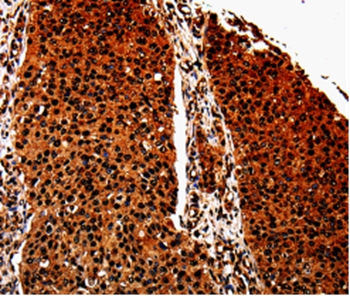

Product Image

| IHC | 1/50-1/200 |